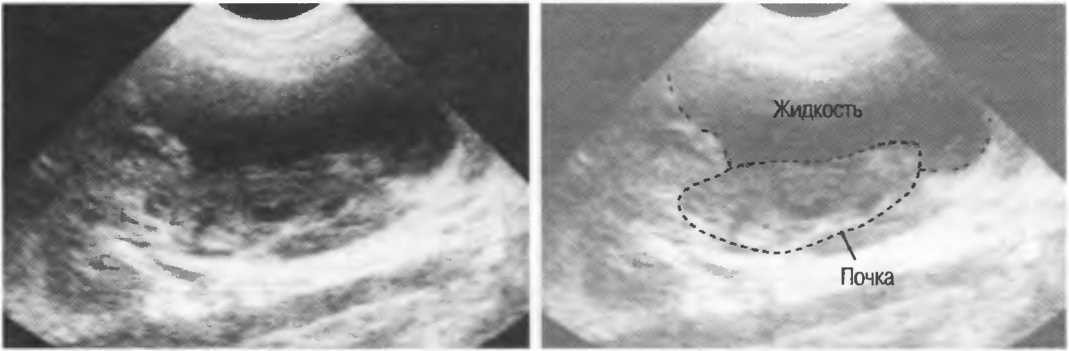

Акустическое усиление и акустическая тень

Чистые жидкости проводят ультразвуковой сигнал без существенного ослабления, поэтому отраженные эхосигналы, идущие от тканей, расположенных за жидкостью, обычно усилены (более яркие). Этот феномен известен как «акустическое усиление» (рис. 10а). Прием достаточного количества жидкости для заполнения желудка дает смещение кишечника, содержащего газ, и тем самым создает акустическое окно. Это особенно полезно для визуализации тела и хвоста поджелудочной железы.